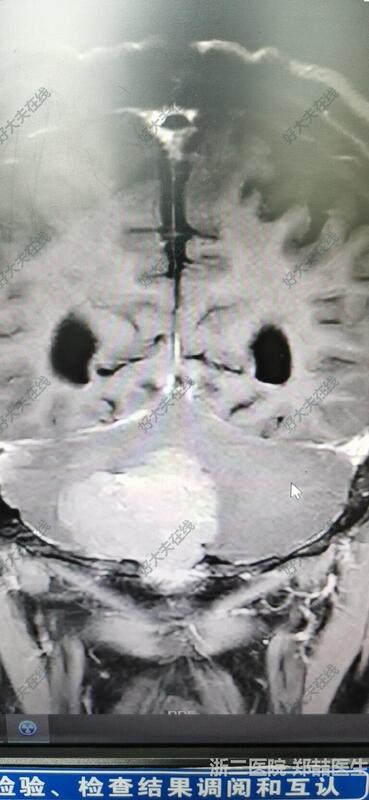

71岁男性,头晕1个月,行走不稳,伴恶心呕吐。头磁共振检查发现后颅窝占位。我院报告淋巴瘤或髓母细胞瘤。个人考虑脑膜瘤可能大,基底广泛。

后正中入路,切除肿瘤,基底广泛,冰冻考虑脑膜瘤。

患者恢复良好,可下地活动,头晕好转,无其他不适。头磁共振复查提示肿瘤全切。